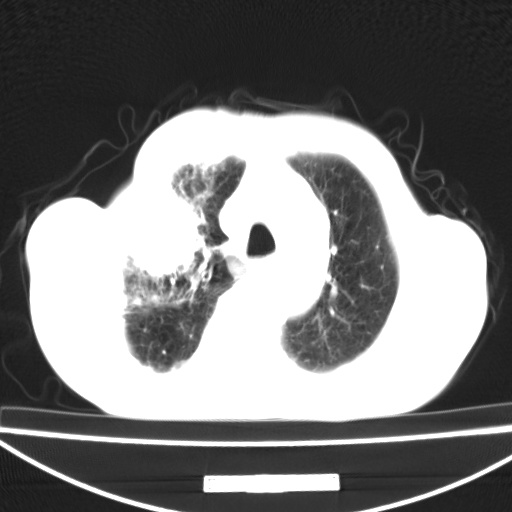

标题: CT13796:请会诊右上费病变!

患者男80岁,反复咳嗽多年,咳喘伴咯血1月

右上肺周围型肺癌伴肺门淋巴结转移.右上肺继发型肺结核.

右上肺周围型肺癌伴肺门淋巴结转移

右肺上叶占位性病变,考虑周围型肺癌,肺门淋巴结转移。要是能提供更多的临床资料就好了,以供鉴别诊断。

右肺尖周围型肺癌伴肺门淋巴结肿大

右肺上叶占位性病变,考虑周围型肺癌,肺门淋巴结转移。

考虑为:右肺上叶肺癌伴阻塞性肺炎、右肺门及纵膈淋巴结转移。